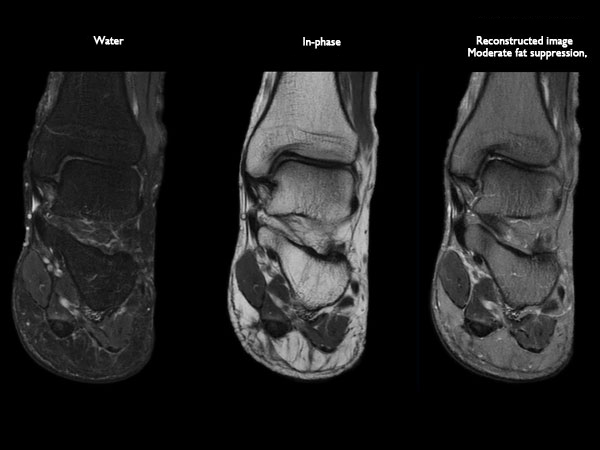

Orthopedic imaging with mDIXON XD TSE